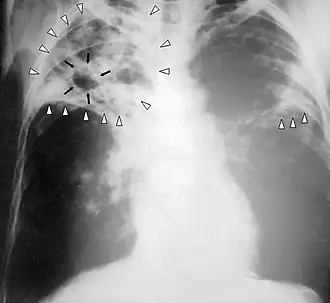

La modalité de diagnostic radiologique se révèle très utile et indiquée comme étant un examen de première intention en cas de tuberculose pulmonaire et ostéoarticulaire[78]. Cela est justifié par les images radiologiques plus ou moins spécifiques à la tuberculose. La littérature rapporte que la spécificité varie de 27 à 81 % selon l’étude. Les imageries idéales et révélatrices de la tuberculose répondent à certains attributs dont le premier est lié au siège. En raison de l’affinité que les BK ont envers les régions aérées, la lésion radiologique est souvent observée dans les parties hautes des poumons. Néanmoins, l’image radiographique peut contenir différentes formes :

- infiltrat : traduisant des lésions débutantes de l’infection via une opacité peu dense, hétérogène et étendue ;

- nodule : granulome de taille variable, isolé ou groupé ;

- tuberculome : nodule isolé pseudotumoral ;

- caverne : excavation par perte de substance au sein d’un infiltrat, aux parois épaisses.

Le terme « tuberculose » est utilisé pour la première fois par Johann Lukas Schönlein en 1839[5]. Il est issu du nom de la lésion unitaire de la maladie, le « tubercule », utilisé depuis le XVIIe siècle et formé depuis le latin tuber signifiant « excroissance »[5]. La tuberculose « miliaire » (caractérisée par la dissémination de très nombreux nodules de petite taille dans les deux poumons) tire son nom de la ressemblance de ces nodules avec des grains de millet[5].